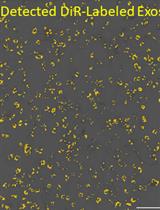

Graphical overview of extracellular vesicle (EV) isolation from plasma samples. (A) Flowchart of the isolation of extracellular vesicles from plasma, detailing plasma preparation and EV purification. (B) Transmission electron microscopy (TEM) image of EVs isolated from human plasma samples. Scale bar, 100 nm.

3. ExoView R200 platform (Software, ExoViewer 2.5.0)